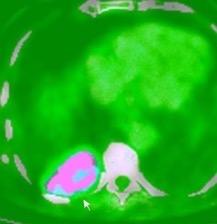

100. TUMOR FANTASMA

102. TUMOR FANTASMA. HEMATOCELE

En relación con trasudados tabicados. Insuficiencia cardiaca

Hipoalbuminemia

Cirrosis / Fallo renal.

Operado aneurisma (prótesis). Líquido tabicado en cisuras

Derrame pleural “encapsulado”

“Tumor fantasma”

Asociado a fallo cardiaco. ( “Pleuritis adhesiva”). Buch KP. Chest. 2000